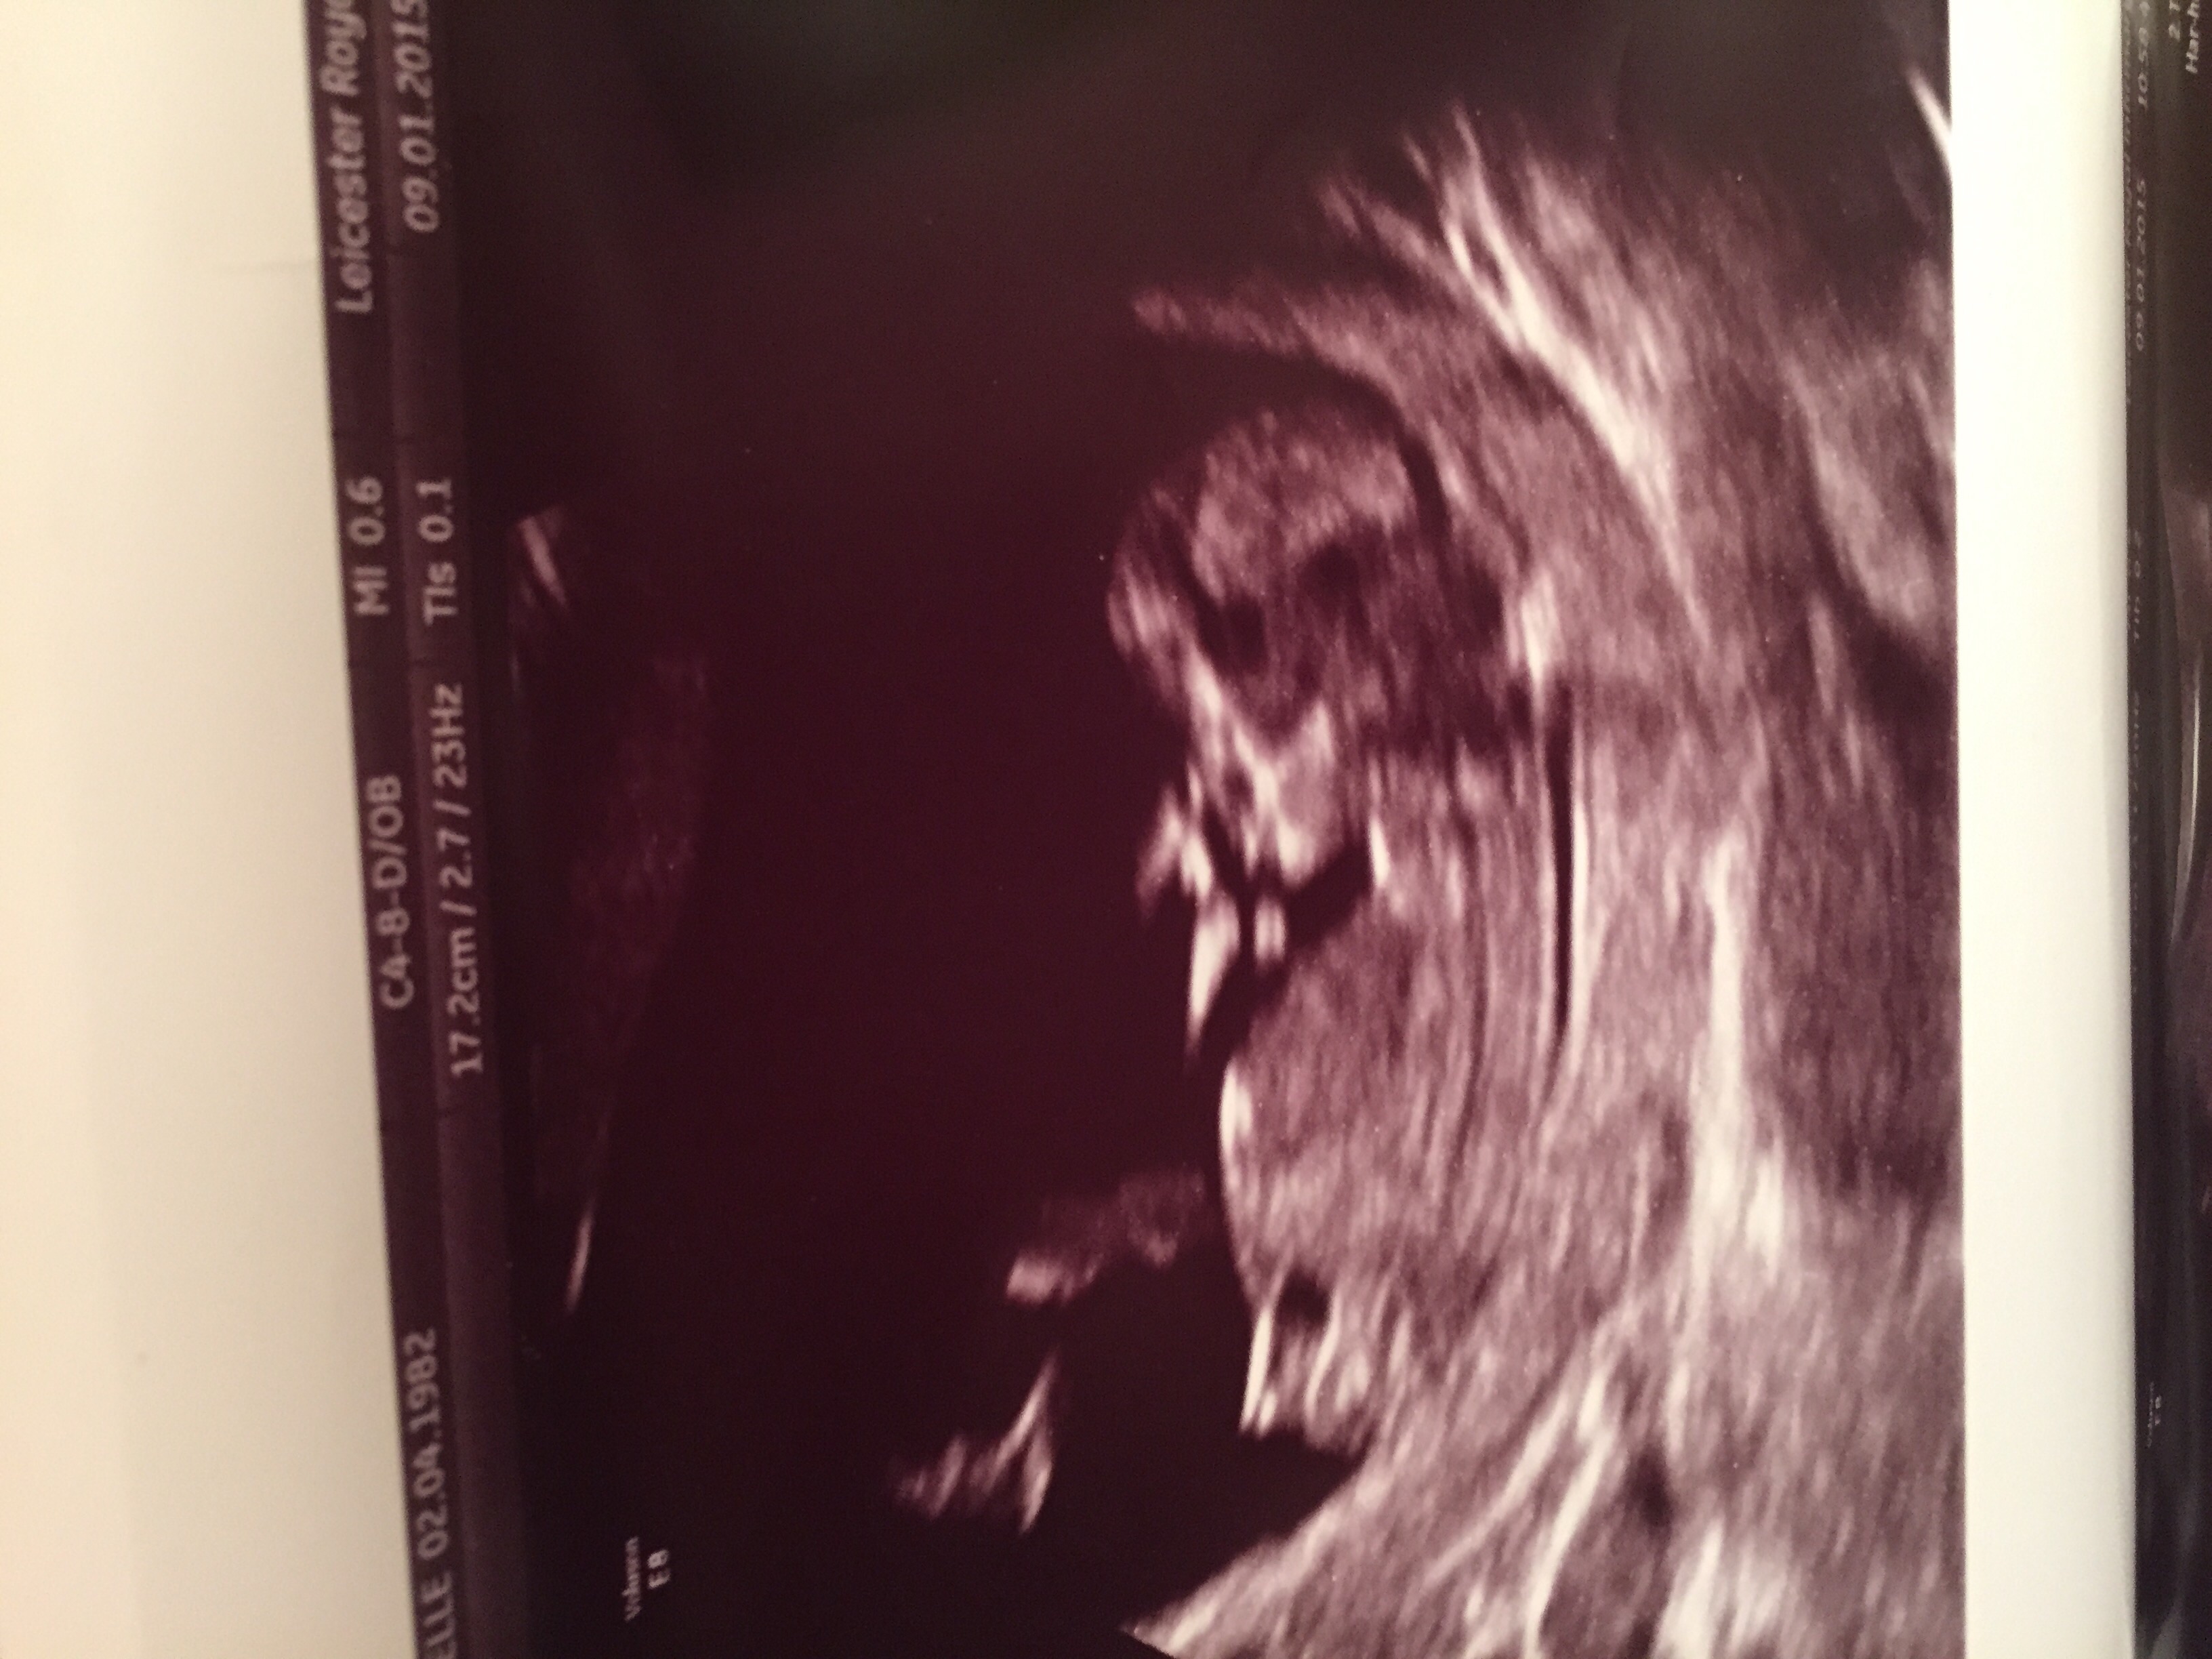

Looks girly

Yes would say girl :)

Girly but still a little early

Girly :)

girl